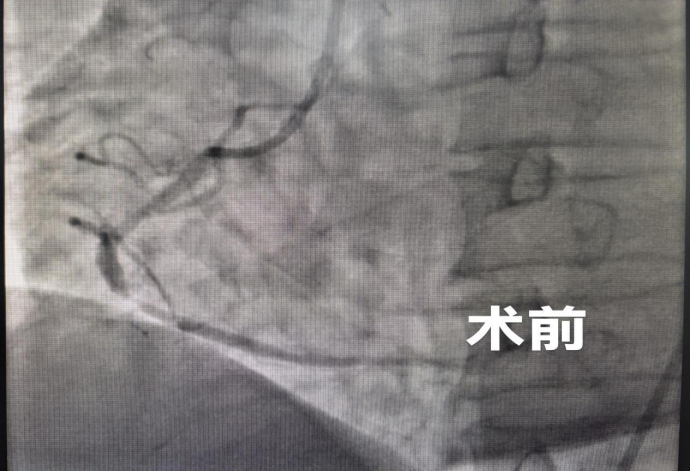

心跳虽已恢复,但患者病情仍不稳定。医院迅速启动急性心梗绿色通道,患者被第一时间送入介入导管室。心血管内科手术团队立即开展急诊冠脉造影+右冠状动脉PCI手术,精准定位堵塞血管,迅速开通血管,恢复心肌供血,从根本上解除致命威胁。手术团队配合默契、操作精准流畅,顺利完成手术。